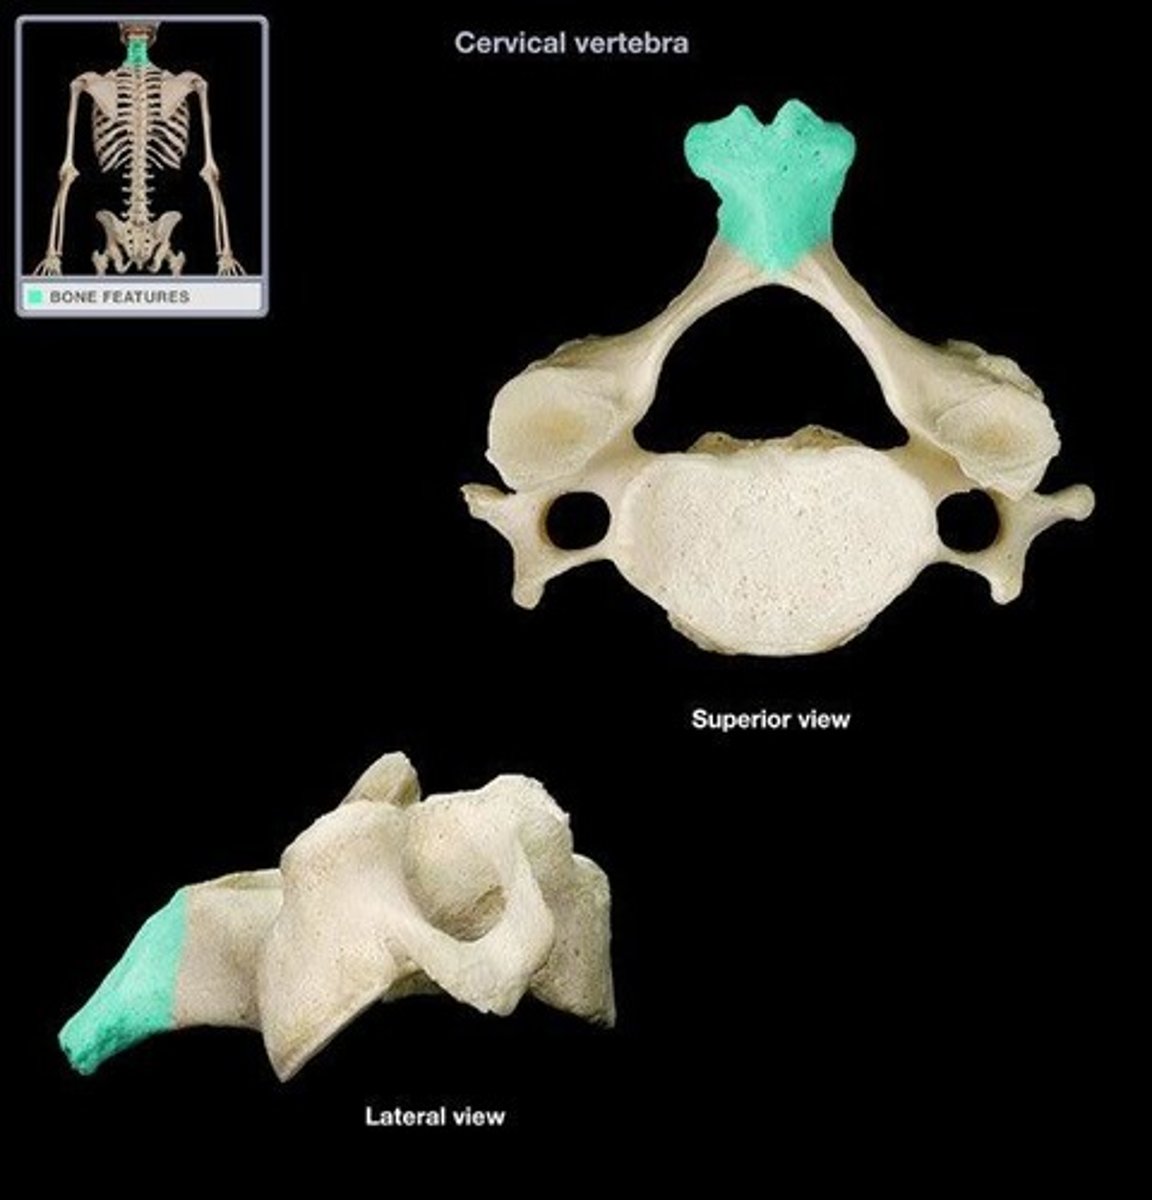

What are the unique characteristics of the cervical spine?

- transverse foramina

- bifid spinous process

- overlapping vertical bodies

Which of the foramina run vertically?

On the cervical vertebrae the spinous processes are short and have double pointed _____ tips

bifid